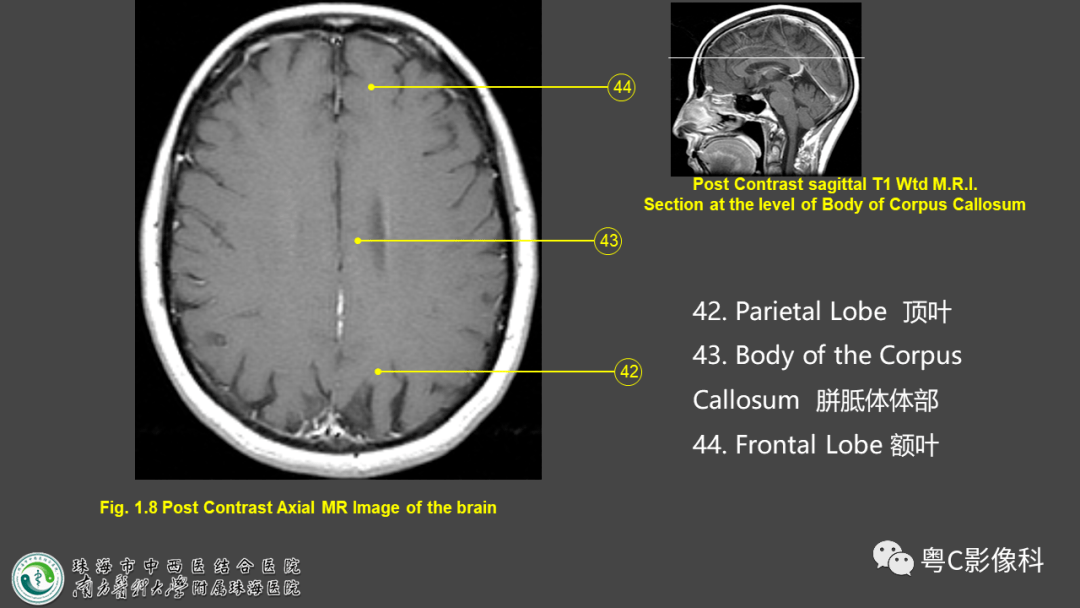

影像解剖影像技术颅脑mri平扫扫描方案